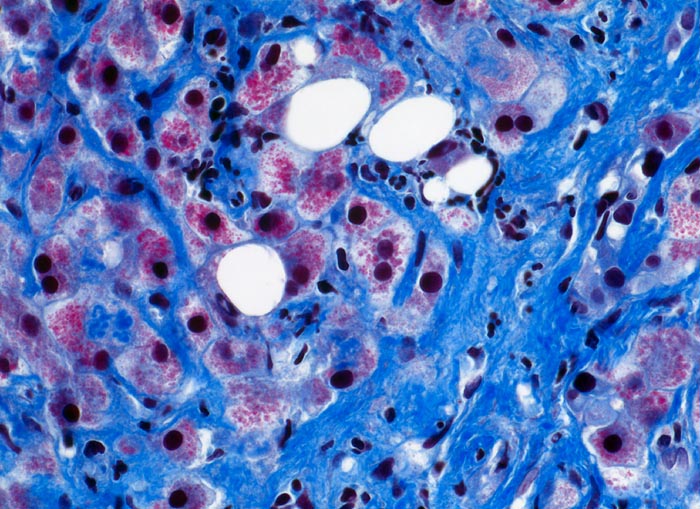

PathoPic ID 4950 - hochfloride chronische sklerosierende alkoholische Steatohepatitis

hochfloride chronische sklerosierende alkoholische Steatohepatitis

Ausgeprägte perizelluläre Fibrose. Einzelne grobtropfig verfettete Hepatozyten. Gemischtes Entzündungsinfiltrat mit Beteiligung zahlreicher neutrophiler Granulozyten. Die Hepatozyten enthalten zahlreiche rote kugelige Einschlüsse (=Megamitochondrien), ein Teil enthält

Mallory Körperchen.

Alkoholabusus

Histologie

400